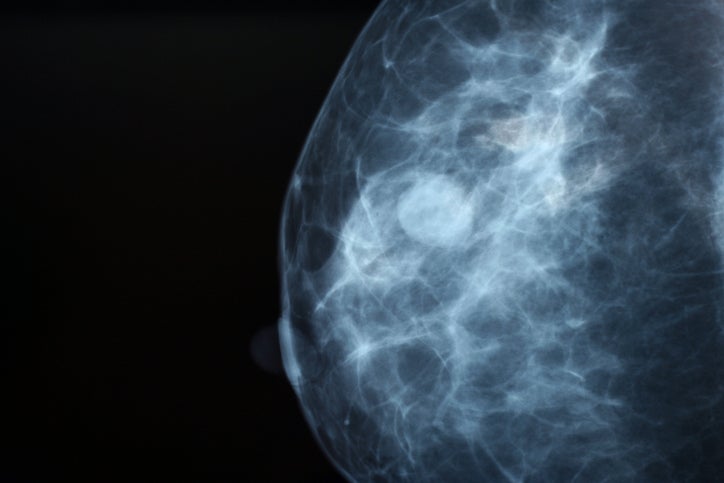

Mammographic imaging guidance

A mammogram will be carried out with the breast placed between two plates and compressed, and the radiologist will find the abnormality. The breast remains compressed for the duration of the procedure. The breast is washed with antiseptic and the radiologist will place a very fine needle into the breast with local anaesthetic to numb the area where the hookwire is to be inserted.

The radiologist will then insert a fine needle into the breast tissue that is to be removed. Mammographic images are taken to check the needle is in the correct position and the needle is adjusted as required. Once the needle is in the correct position, a fine wire is passed down the centre of the needle and the needle is removed, leaving the wire in place. A final mammogram is carried out to show the surgeon where the tip of the wire lies in relation to the abnormality that is to be removed.